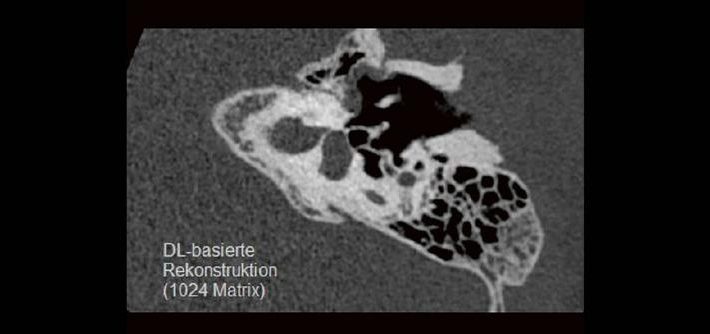

DEEP-Learning-Rekonstruktion in der Neuroradiologie (Webinar | Online)

Professor Dr. med. Marc Brockmann WEITERENTWICKLUNGEN VON KOPF BIS FUSS BEIM VC Oberstarzt Dr. med. Stephan Waldeck DEEP-LEARNING-REKONSTRUKTION IN DER NEURORADIOLOGIE Die CT ist ein essentielles Routine-Verfahren in der Neuroradiologie. Bei steigender Bildqualität konnte die Röntgendosis mit neuen Technologien in der letzten Dekade deutlich gesenkt werden, was für die zielgerichtete und möglichst schonende Behandlung von […]